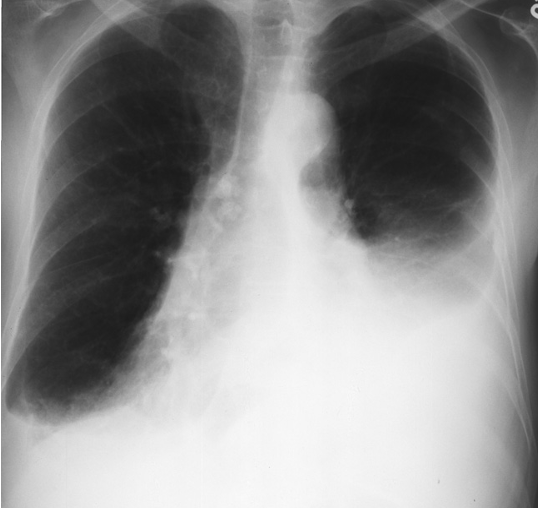

Pericardial effusion. The heart is greatly enlarged. The outline is well defined and the shape globular (Flask - bottle). The lungs are normal. The cause in this case was a viral pericarditis. // Flask shaped, pericardial effusion